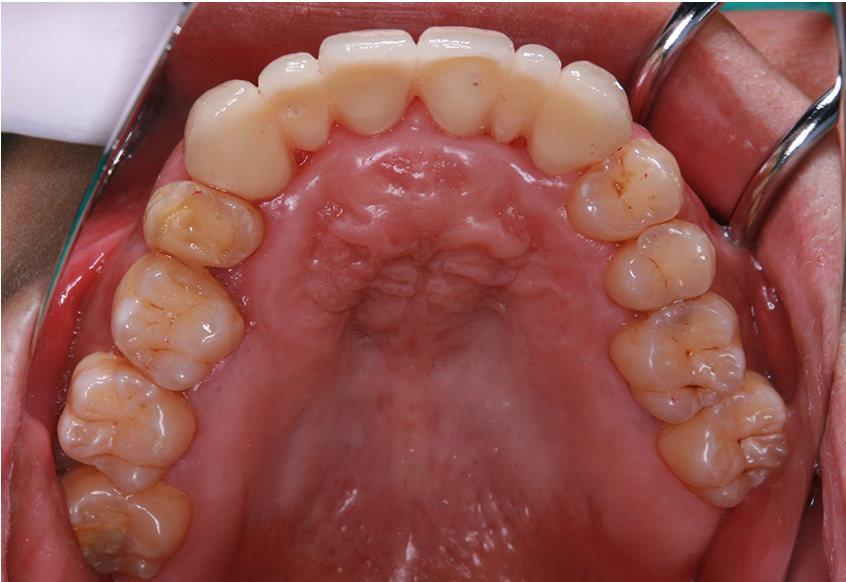

6ヵ月経過すると、矯正治療を終了し、前歯に被せ物の治療を行いました。

最初のお口の中 2025/3/22

被せ物装着

| 治療内容 | 上顎側切歯を2本抜歯した後、上顎の歯にブラケットを装着し、ワイヤー、矯正用ゴムで歯の移動を行いました。その後、被せ物の治療を行って治療を終了しています。 |